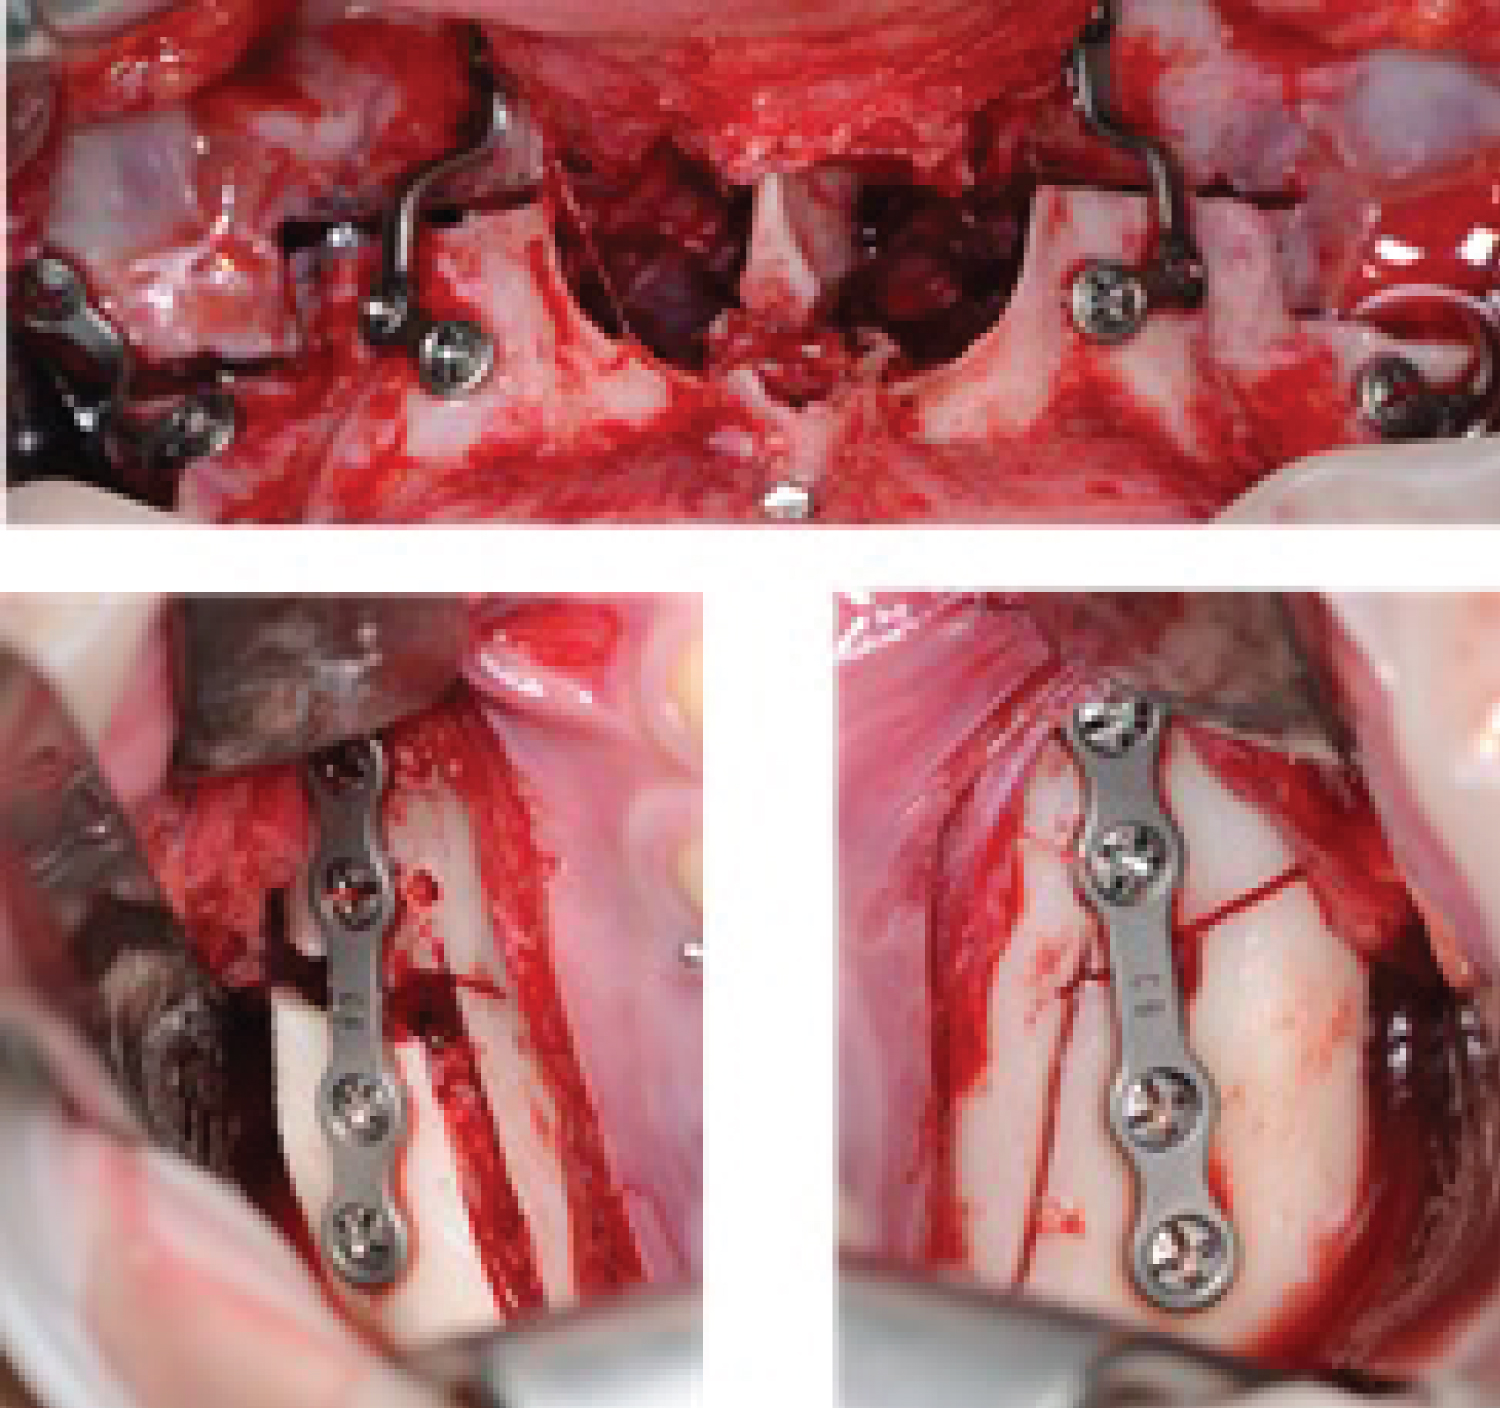

Figure 3: Patient 1: a) Le Fort 1 advance and descent osteotomy; b,c) Osteotomy sagittal branch of mandibular. View Figure 3

Figure 4: a) Chin decoration showing true hypermentonism; B) Reciprocating saw ostectomy; C) Post ostectomy surgical site and correction Hypermentonism. View Figure 4

Figure 8: a) Le Fort 1 advance and descent ostectomy; b,c) Sagittal ostectomy of mandibular branch. View Figure 8

Figure 9: Patient 2: a) Chin decoration where hypermentonism is evidenced true; b) Ostectomy with reciprocating saw; c) Post ostectomy surgical site and Hypermentonism correction. View Figure 9